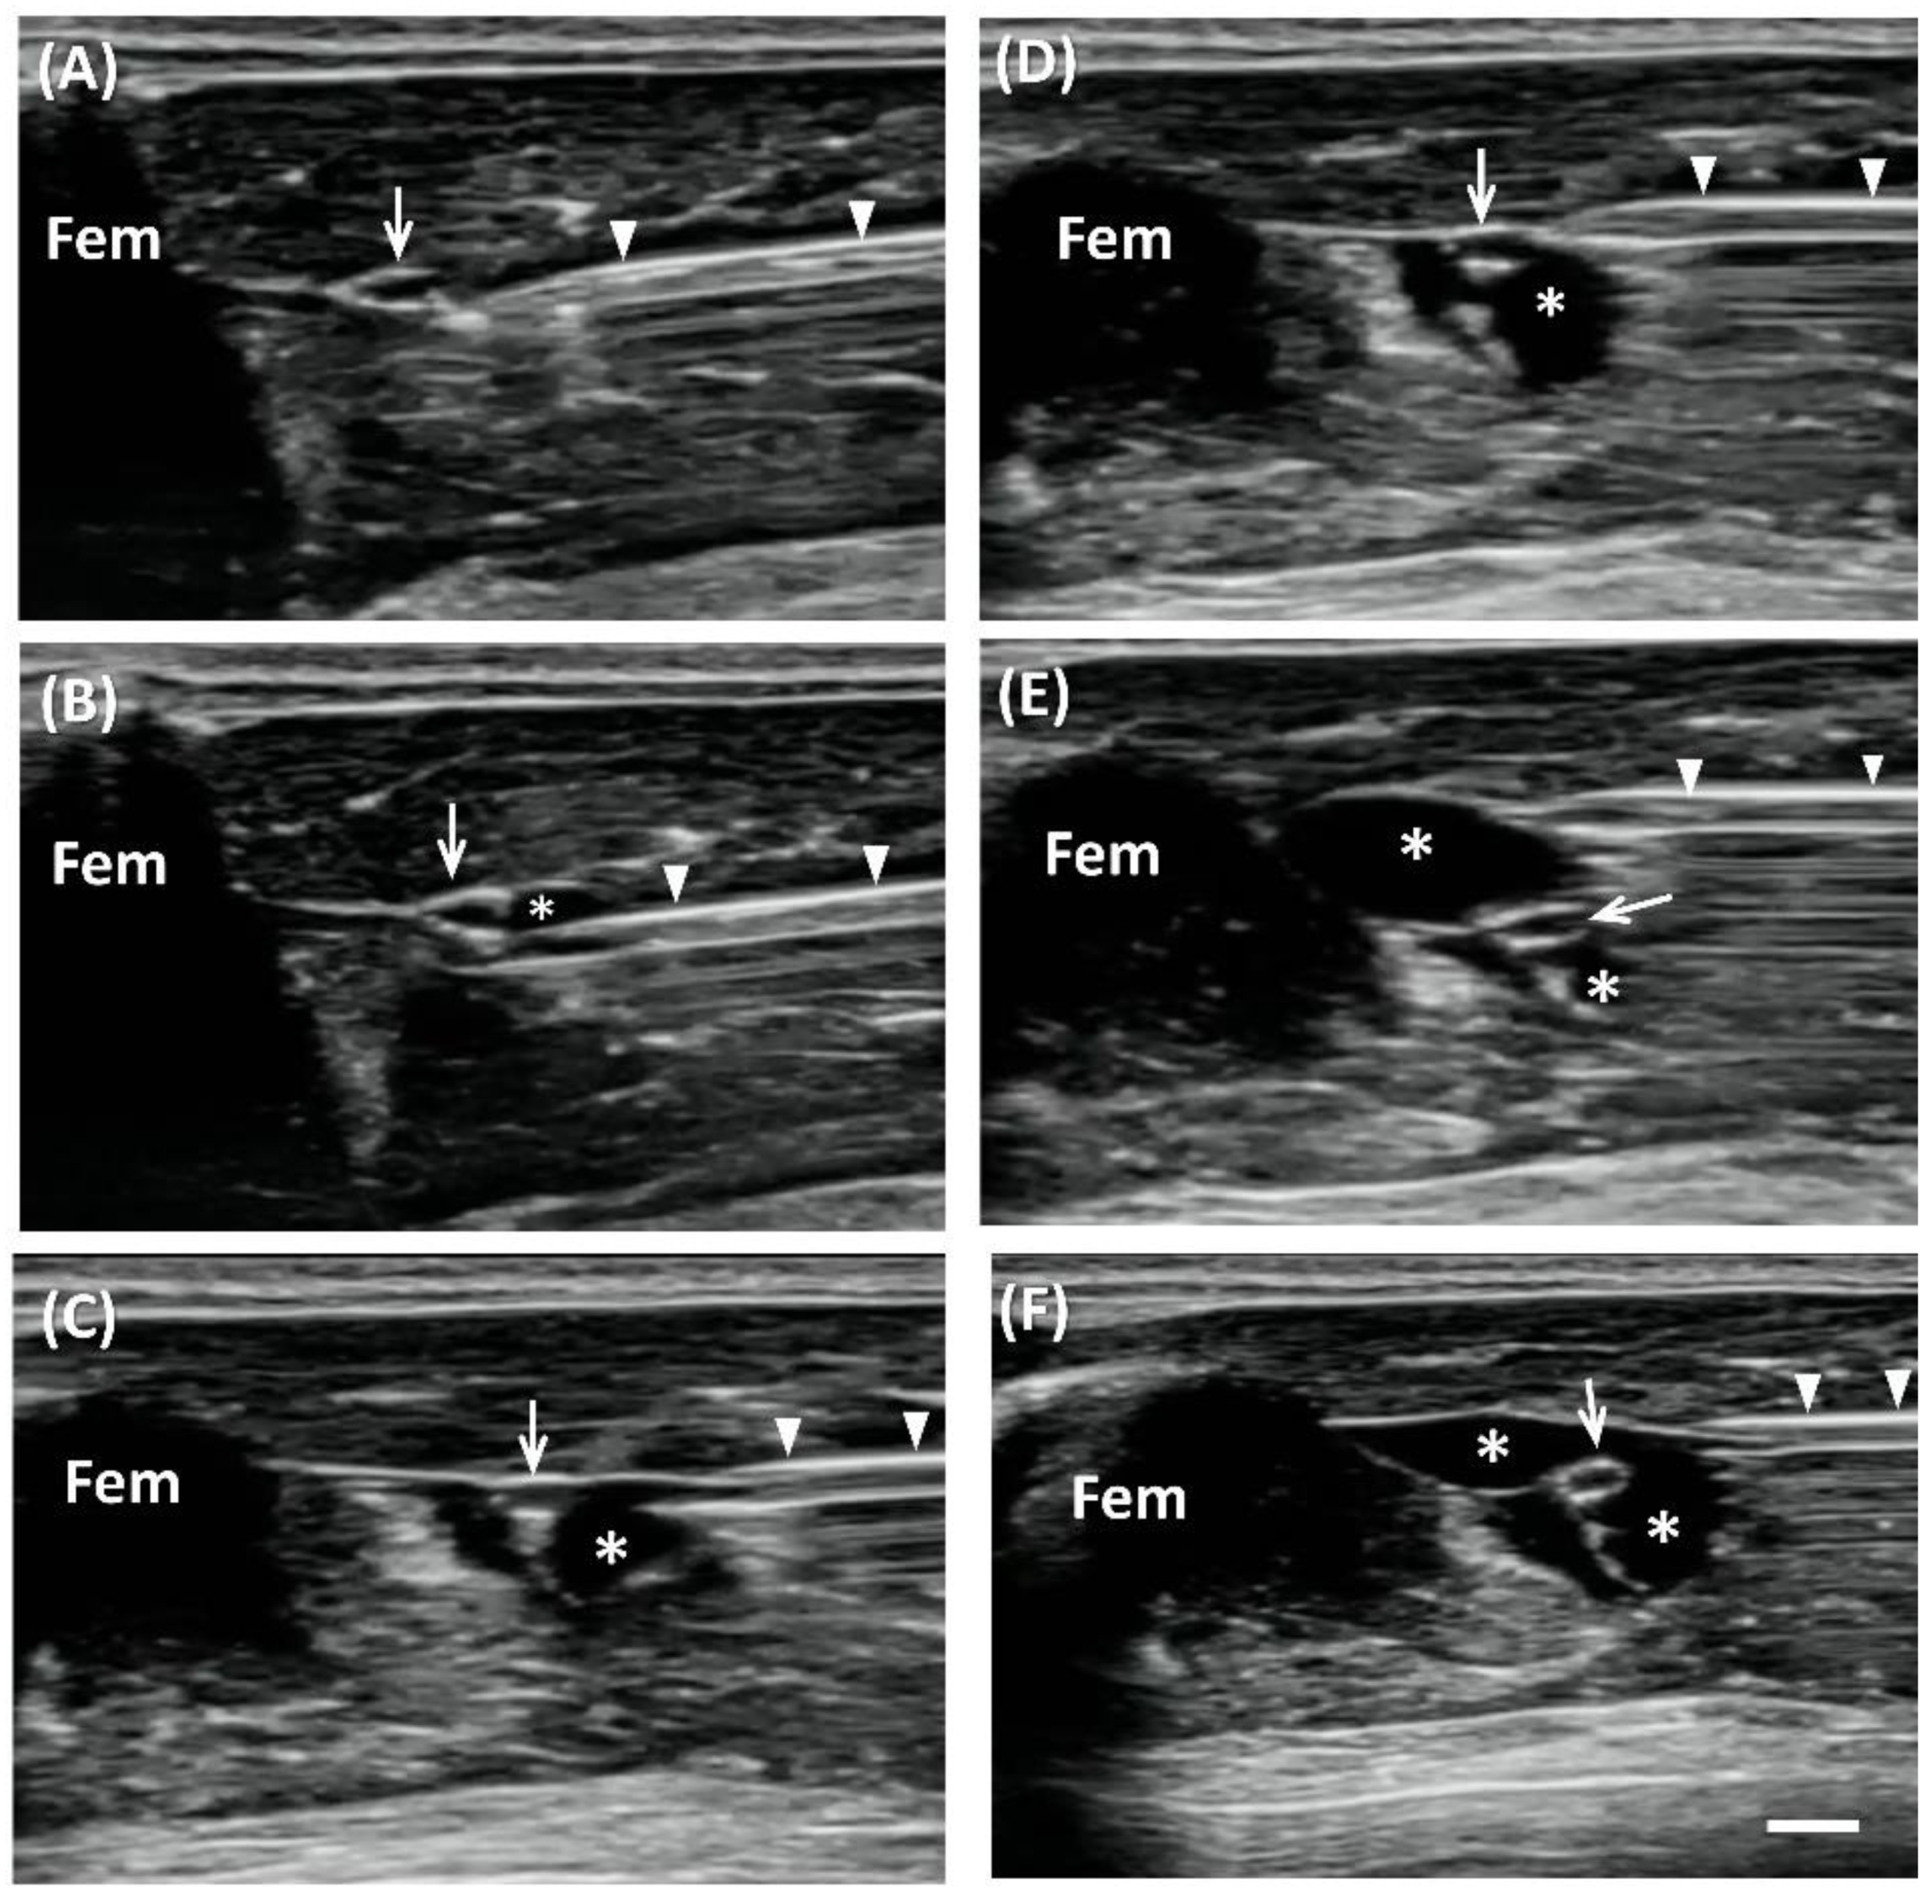

2.1. US-Guided Perineural Injection

In total, 11 rats were used in the experiment. US imaging demonstrated perineural delivery of hydrogel, which appeared as homogeneous hypoechoic immediately postinjection, distributed both superficially and at deep sciatic nerve locations (Figure 1). The middle part of the sciatic nerve was completely surrounded by the hydrogel. Retention of perineural hydrogel at days 7 and 14 was confirmed sonographically. The hydrogel appeared to be slightly heterogeneous echogenic, possibly owing to the partial degradation and tissue reaction. Note that the surrounding hydrogel displaced the sciatic nerve, which became tortuous 7 and 14 days postinjection. In addition, the hydrogel-injected nerves appeared swollen proximal to the injection site, and thus demonstrated the pathognomonic feature of EN (Figure 2).

US-guided injection was performed with short-axis acquisitions. The needle was inserted in plane with the transducer in a posterior–anterior direction and slowly advanced toward the nerve. Hydrogel or saline was injected after placing the needle tip between the nerve and fascia. The injectate (1 mL total) was dispersed in superficial and deep regions with respect to the nerve equally by repositioning the needle so that the injectate completely surrounded the nerve (Figure 1).

Figure 1. Ultrasound (US)-guided perineural injection of hydrogel. Short-axis view, in-plane approach of US-guided perineural injection of hydrogel (asterisks) showing the insertion of the needle (arrowheads) in the deep regions around the sciatic nerve (arrow) initially (AC), and then superficially (DF) (Fem, femur) (Scale bar: 1 mm).